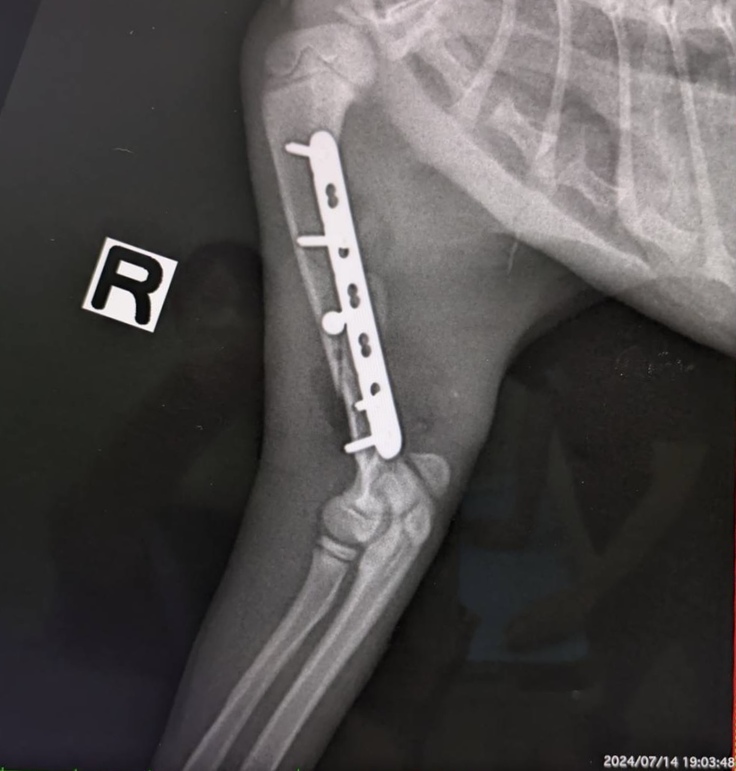

【右上腕 術後】

【本日】こちらはまだ隙間があります。